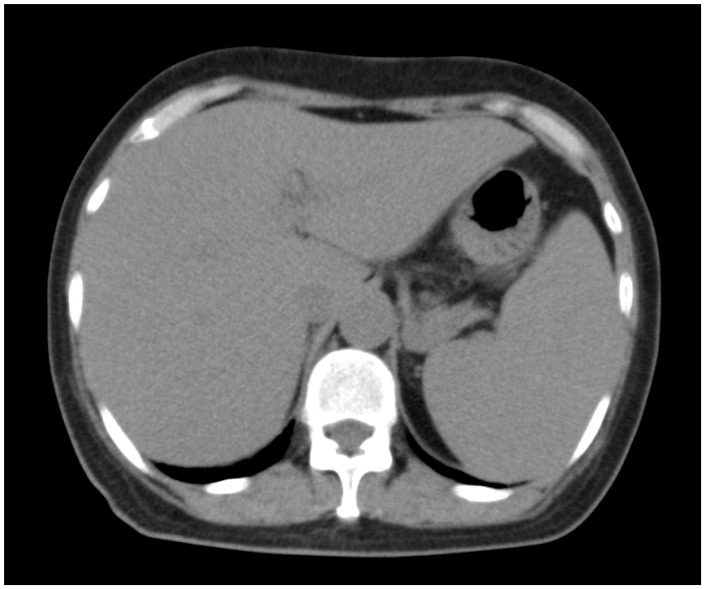

血管内淋巴瘤(IVL)是一种罕见的淋巴瘤亚型,主要来自b细胞。一些IVL病例被报道为NK/T细胞起源(IVNKTL)。已知这些病例是致命的,特别是当出现全身性症状时。我们报告了一例IVNKTL患者,最初治疗难治,接受了自体造血干细胞移植(auto-HSCT)。她保持完全缓解(CR)超过8年。我们的病例可能支持自体造血干细胞移植治疗化疗敏感的IVNKTL的证据。

Intravascular lymphoma (IVL) is a rare subtype of lymphoma, mostly of B-cell origin. A few cases of IVL have been reported as having NK/T cell origins (IVNKTL). These cases are known to be fatal, especially when systemic symptoms are present. We report the case of a patient of IVNKTL who was refractory to initial treatment and received autologous hematopoietic stem cell transplantation (auto-HSCT). She has maintained complete remission (CR) for over eight years. Our case might support the evidence of auto-HSCT for the treatment of IVNKTL with chemosensitivity.